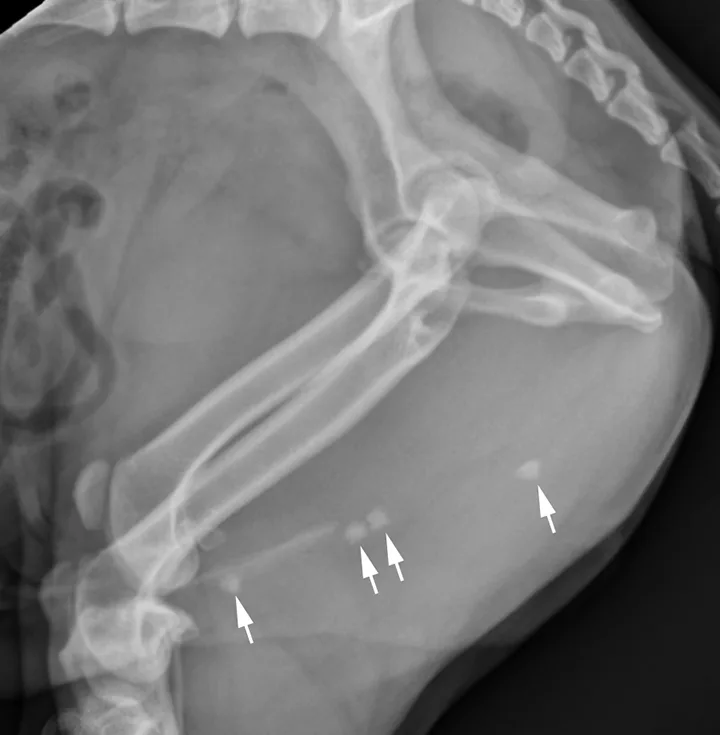

FIGURE 11A

Lateral radiograph of a male dog collimated to include the urinary bladder and os penis. Note the well-defined mineral opacity just proximal to and at the same level as the base of the os penis—a separate center of ossification (arrow). Also note the two soft tissue opaque nodules summating with the prepuce, presumed to be small nipples (arrowheads).

A separate center of ossification associated with the os penis may mimic a urethral calculus (Figure 11 A and B). A separate center of ossification can be seen at either end of the os penis and will be in line with the os penis. A calculus within the penile urethra would be seen ventral to the os penis in the location of the urethra. Contrast urethrography can be a helpful way to differentiate between a separate center of ossification and urethral calculus (Figure 11C).